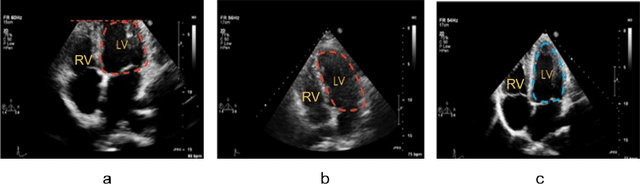

Abstract:Standard views in two-dimensional echocardiography are well established but the quality of acquired images are highly dependent on operator skills and are assessed subjectively. This study is aimed at providing an objective assessment pipeline for echocardiogram image quality by defining a new set of domain-specific quality indicators. Consequently, image quality assessment can thus be automated to enhance clinical measurements, interpretation, and real-time optimization. We have developed deep neural networks for the automated assessment of echocardiographic frame which were randomly sampled from 11,262 adult patients. The private echocardiography dataset consists of 33,784 frames, previously acquired between 2010 and 2020. Deep learning approaches were used to extract the spatiotemporal features and the image quality indicators were evaluated against the mean absolute error. Our quality indicators encapsulate both anatomical and pathological elements to provide multivariate assessment scores for anatomical visibility, clarity, depth-gain and foreshortedness, respectively.

Abstract:Echocardiography image quality assessment is not a trivial issue in transthoracic examination. As the in vivo examination of heart structures gained prominence in cardiac diagnosis, it has been affirmed that accurate diagnosis of the left ventricle functions is hugely dependent on the quality of echo images. Up till now, visual assessment of echo images is highly subjective and requires specific definition under clinical pathologies. While poor-quality images impair quantifications and diagnosis, the inherent variations in echocardiographic image quality standards indicates the complexity faced among different observers and provides apparent evidence for incoherent assessment under clinical trials, especially with less experienced cardiologists. In this research, our aim was to analyse and define specific quality attributes mostly discussed by experts and present a fully trained convolutional neural network model for assessing such quality features objectively.